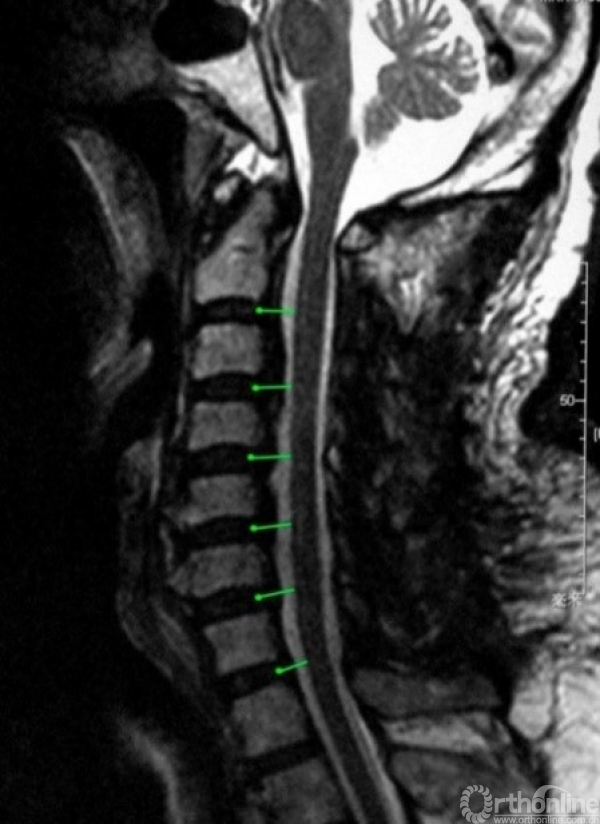

针对“门轴”的固定方式以及后方软组织结构破坏等问题衍生了多种改良术式,但这些术式的减压原理相同:(1)直接减压效应:直接去除来自脊髓后方的压迫(如黄韧带肥厚、骨化、钙化)或纠正发育性颈椎管狭窄;(2)间接减压效应:在临床实践中,人们发现椎管扩大之后,脊髓会发生后移,从而消除或减弱了来自前方的压迫(如椎间盘突出、后纵韧带骨化、椎体后缘骨赘等)对脊髓的影响(图1)。

图1